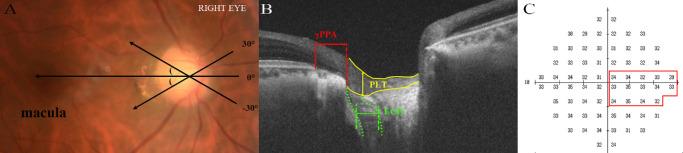

This retrospective study measured γPPA length, prelaminar tissue (PLT) thickness, and lamina cribrosa (LC) defects' width in HM eyes with central VF defects by swept-source optical coherence tomography (OCT). The central VF was assessed by using the Humphrey Field Analyzer 10-2 program, and average light sensitivity in the papillomacular bundle region (C1 region) and mean deviation (MD) values were calculated. Interactions among the central VF and structural abnormalities were analyzed using correlation tests and linear regression.

Forty-five eyes from 45 patients were included. PLT thickness was positively associated with light sensitivity in the C1 region and MD values, whereas γPPA was associated only with MD values. LC defects showed no association with either the C1 region or MD values. LC defects' width was negatively correlated with γPPA length. Stratified analysis showed that in the group with γPPA length ≥763 µm, PLT thickness was positively associated, and γPPA length was negatively associated with the C1 region and MD values. No such associations were found when the γPPA length was <763 µm. The association between LC defects with central VF remained nonsignificant.